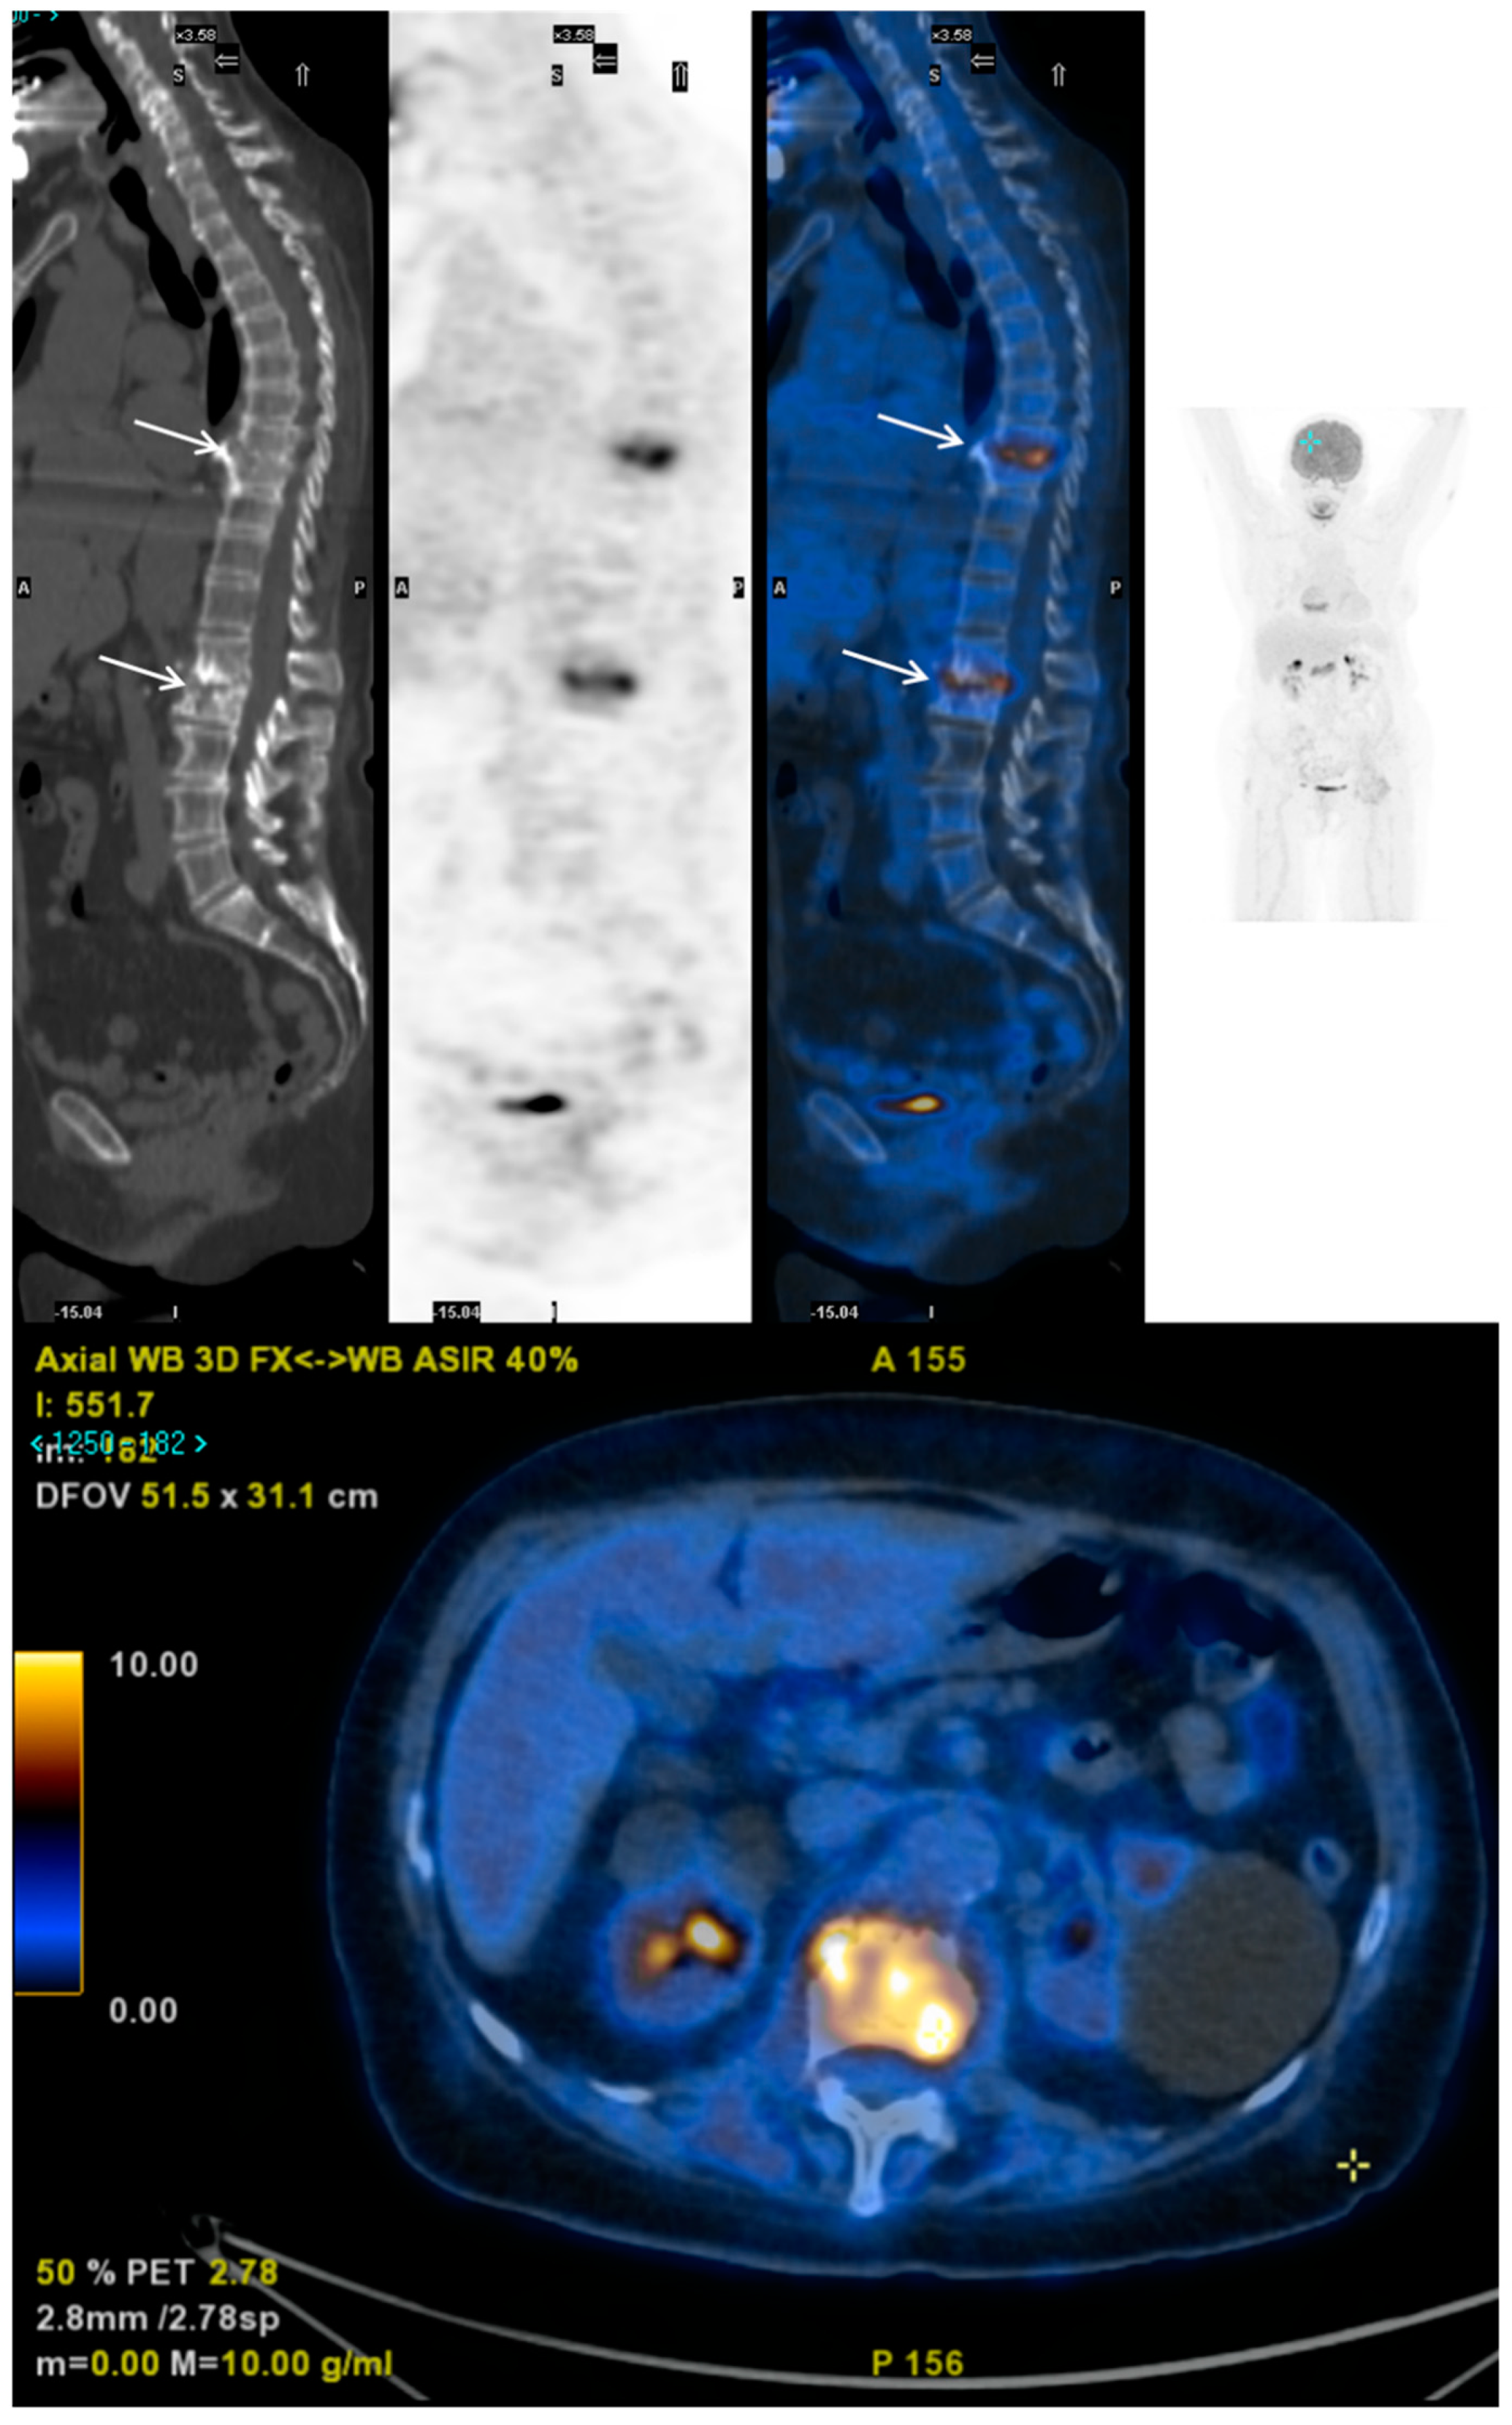

- Fuster, D.; Solà, O.; Soriano, A.; Monegal, A.; Setoain, X.; Tomás, X.; Garcia, S.; Mensa, J.; Rubello, D.; Pons, F. A prospective study comparing whole-body FDG PET/CT to combined planar bone scan with 67Ga SPECT/CT in the Diagnosis of Spondylodiskitis. Clin. Nucl. Med. 2012, 37, 827–832. [Google Scholar] [CrossRef] [PubMed]

- Prodromou, M.L.; Ziakas, P.D.; Poulou, L.S.; Karsaliakos, P.; Thanos, L.; Mylonakis, E. FDG PET is a robust tool for the diagnosis of spondylodiscitis: A meta-analysis of diagnostic data. Clin. Nucl. Med. 2014, 39, 330–335. [Google Scholar] [CrossRef] [PubMed] [Green Version]

- Nanni, C.; Boriani, L.; Salvadori, C.; Zamparini, E.; Rorato, G.; Ambrosini, V.; Gasbarrini, A.; Tumietto, F.; Cristini, F.; Scudeller, L.; et al. FDG PET/CT is useful for the interim evaluation of response to therapy in patients affected by haematogenous spondylodiscitis. Eur. J. Nucl. Med. Mol. Imaging 2012, 39, 1538–1544. [Google Scholar] [CrossRef]

- Kim, S.J.; Pak, K.; Kim, K.; Lee, J.S. Comparing the Diagnostic Accuracies of F-18 Fluorodeoxyglucose Positron Emission Tomography and Magnetic Resonance Imaging for the Detection of Spondylodiscitis: A Meta-analysis. Spine (Phila Pa 1976) 2019, 44, E414–E422. [Google Scholar] [CrossRef] [PubMed]

- Yin, Y.; Liu, X.; Yang, X.; Guo, J.; Wang, Q.; Chen, L. Diagnostic value of FDG-PET versus magnetic resonance imaging for detecting spondylitis: A systematic review and meta-analysis. Spine J. 2018, 18, 2323–2332. [Google Scholar] [CrossRef] [PubMed]